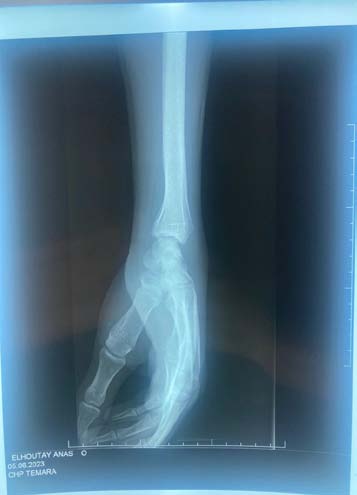

The standard radiographic assessment revealed a scaphoid fracture with an underlying gap, suggesting the possibility of a cyst or pseudarthrosis of the scaphoid (figure 1). The wrist CT scan confirmed the scaphoid fracture with a probable intraosseous cyst (figure 2). The patient underwent surgery via an anterior approach. Careful curettage of the cavity was performed after distraction of the fracture site. The bone defect was filled with autologous cancellous graft harvested from the lower metaphysis of the ipsilateral radius. Fracture stabilization was achieved with 2 pins (figure 3). The histopathological examination of the curettage specimen showed that the cyst wall was lined with flattened fibroblastic cells resembling synovial cells, without true epithelial appearance. There was no mucoid degeneration or myxoid transformation. The patient was immobilized for 2 months in a resin splint. After this period, the hardware was removed under local anesthesia. Several sessions of functional rehabilitation were initiated after plaster removal. At the latest follow-up at 6 months after treatment, the patient had regained good wrist function, with painlessness and resumption of leisure and professional activities.

From a radiological perspective, typical images show osteolytic lesions of a few millimeters in diameter, either solitary or multilobulated, accompanied by a peripheral rim of osteosclerosis [7]. This description corresponds to the lesion observed on our patient's radiographs, along with a discontinuity at the scaphoid neck, indicating a pathological fracture due to weakening of the scaphoid neck. Computed tomography, whether performed with or without contrast agent injection, allows for precise determination of the nature of the intracystic contents and any cortical involvement [1,7]. It also helps establish a surgical protocol by specifying the most appropriate approach, including the preferred surgical access route.